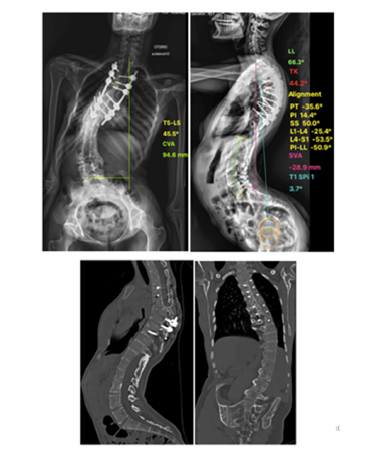

There were no intraoperative or post-operative complications. Operative time was 415 minutes; blood loss was 450cc. The patient spent the first forty-eight post-operative hours in the surgical ICU and was discharged from the hospital after 8 days. The patient was followed for two years. Computed Tomography (CT) performed 6 months after the procedure showed bone fusion. Clinically, the trunk alignment was correct with a consequent improvement in the compensatory mechanisms of the hip and knee (Figure 5). The radiographic parameters of sagittal alignment in the pre- and postoperative period are presented in Table 1 and are illustrated in Figure 6, with improvement of sagittal alignment. Figure 6 shows the radiographic parameters of three years follow up.

Figure 6:a) Anteroposterior. b) Lateral postoperative full-length standing spine radiographs showing significant improvement of the sagittal alignment and spinopelvic parameters. c) Six-month postoperative sagittal and coronal CT reconstruction showing osteotomy healing.